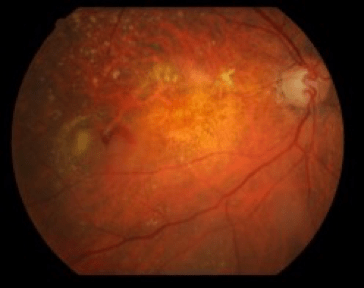

Η ηλιακή ακτινοβολία αποτελείται από υπέρυθρες, υπεριώδεις (UV) και ακτίνες υψηλής ενέργειας που ανήκουν στο ορατό φάσμα (είναι δηλαδή αντιληπτές από εμάς). Οι ακτίνες αυτές προκαλούν βλάβες τόσο στους εξωτερικούς χιτώνες του ματιού, όσο και στον αμφιβληστροειδή χιτώνα στον οποίο απεικονίζεται το είδωλο της εικόνας που βλέπουμε.